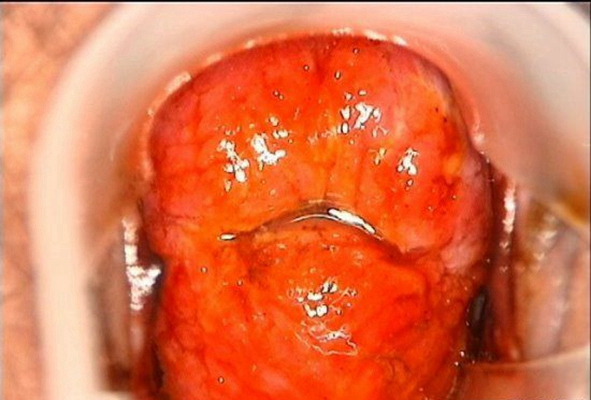

淋病圖片

淋病的症狀 (7)

淋病的症狀 (8)

淋病的症狀 (9)

淋病的症狀 (47)

淋病的症狀 (48)

淋病的症狀 (49)

淋病的症狀 (5)

淋病的症狀 (50)

淋病的症狀 (51)

淋病的症狀 (52)

淋病的症狀 (53)

淋病的症狀 (54)

淋病的症狀 (55)

淋病的症狀 (56)

淋病的症狀 (6)

淋病的症狀 (40)

淋病的症狀 (41)

淋病的症狀 (42)

淋病的症狀 (43)

淋病的症狀 (44)